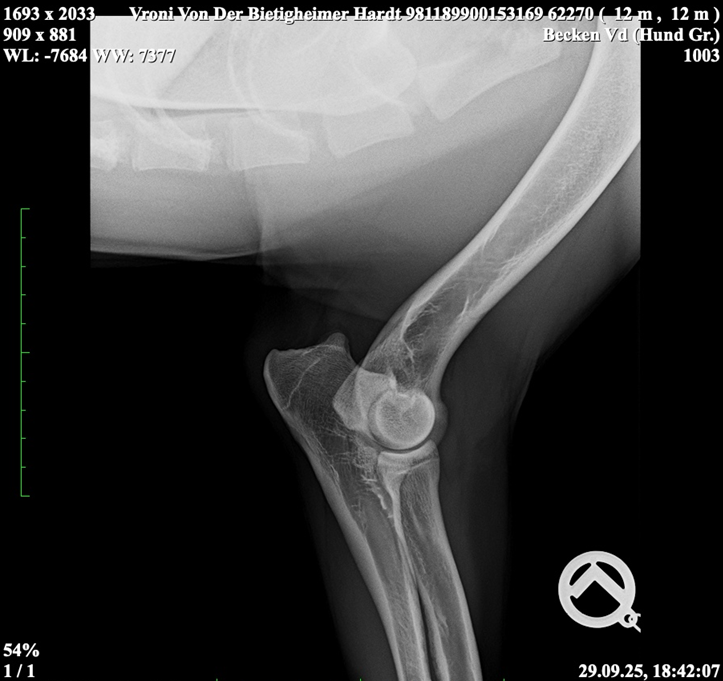

Vroni von der Bietigheimer Hardt

SZ. 2395403; WT: 27.09.2024;

HD ZW: kW25/02 „69“ Größen-ZW: kW25/02 „101!